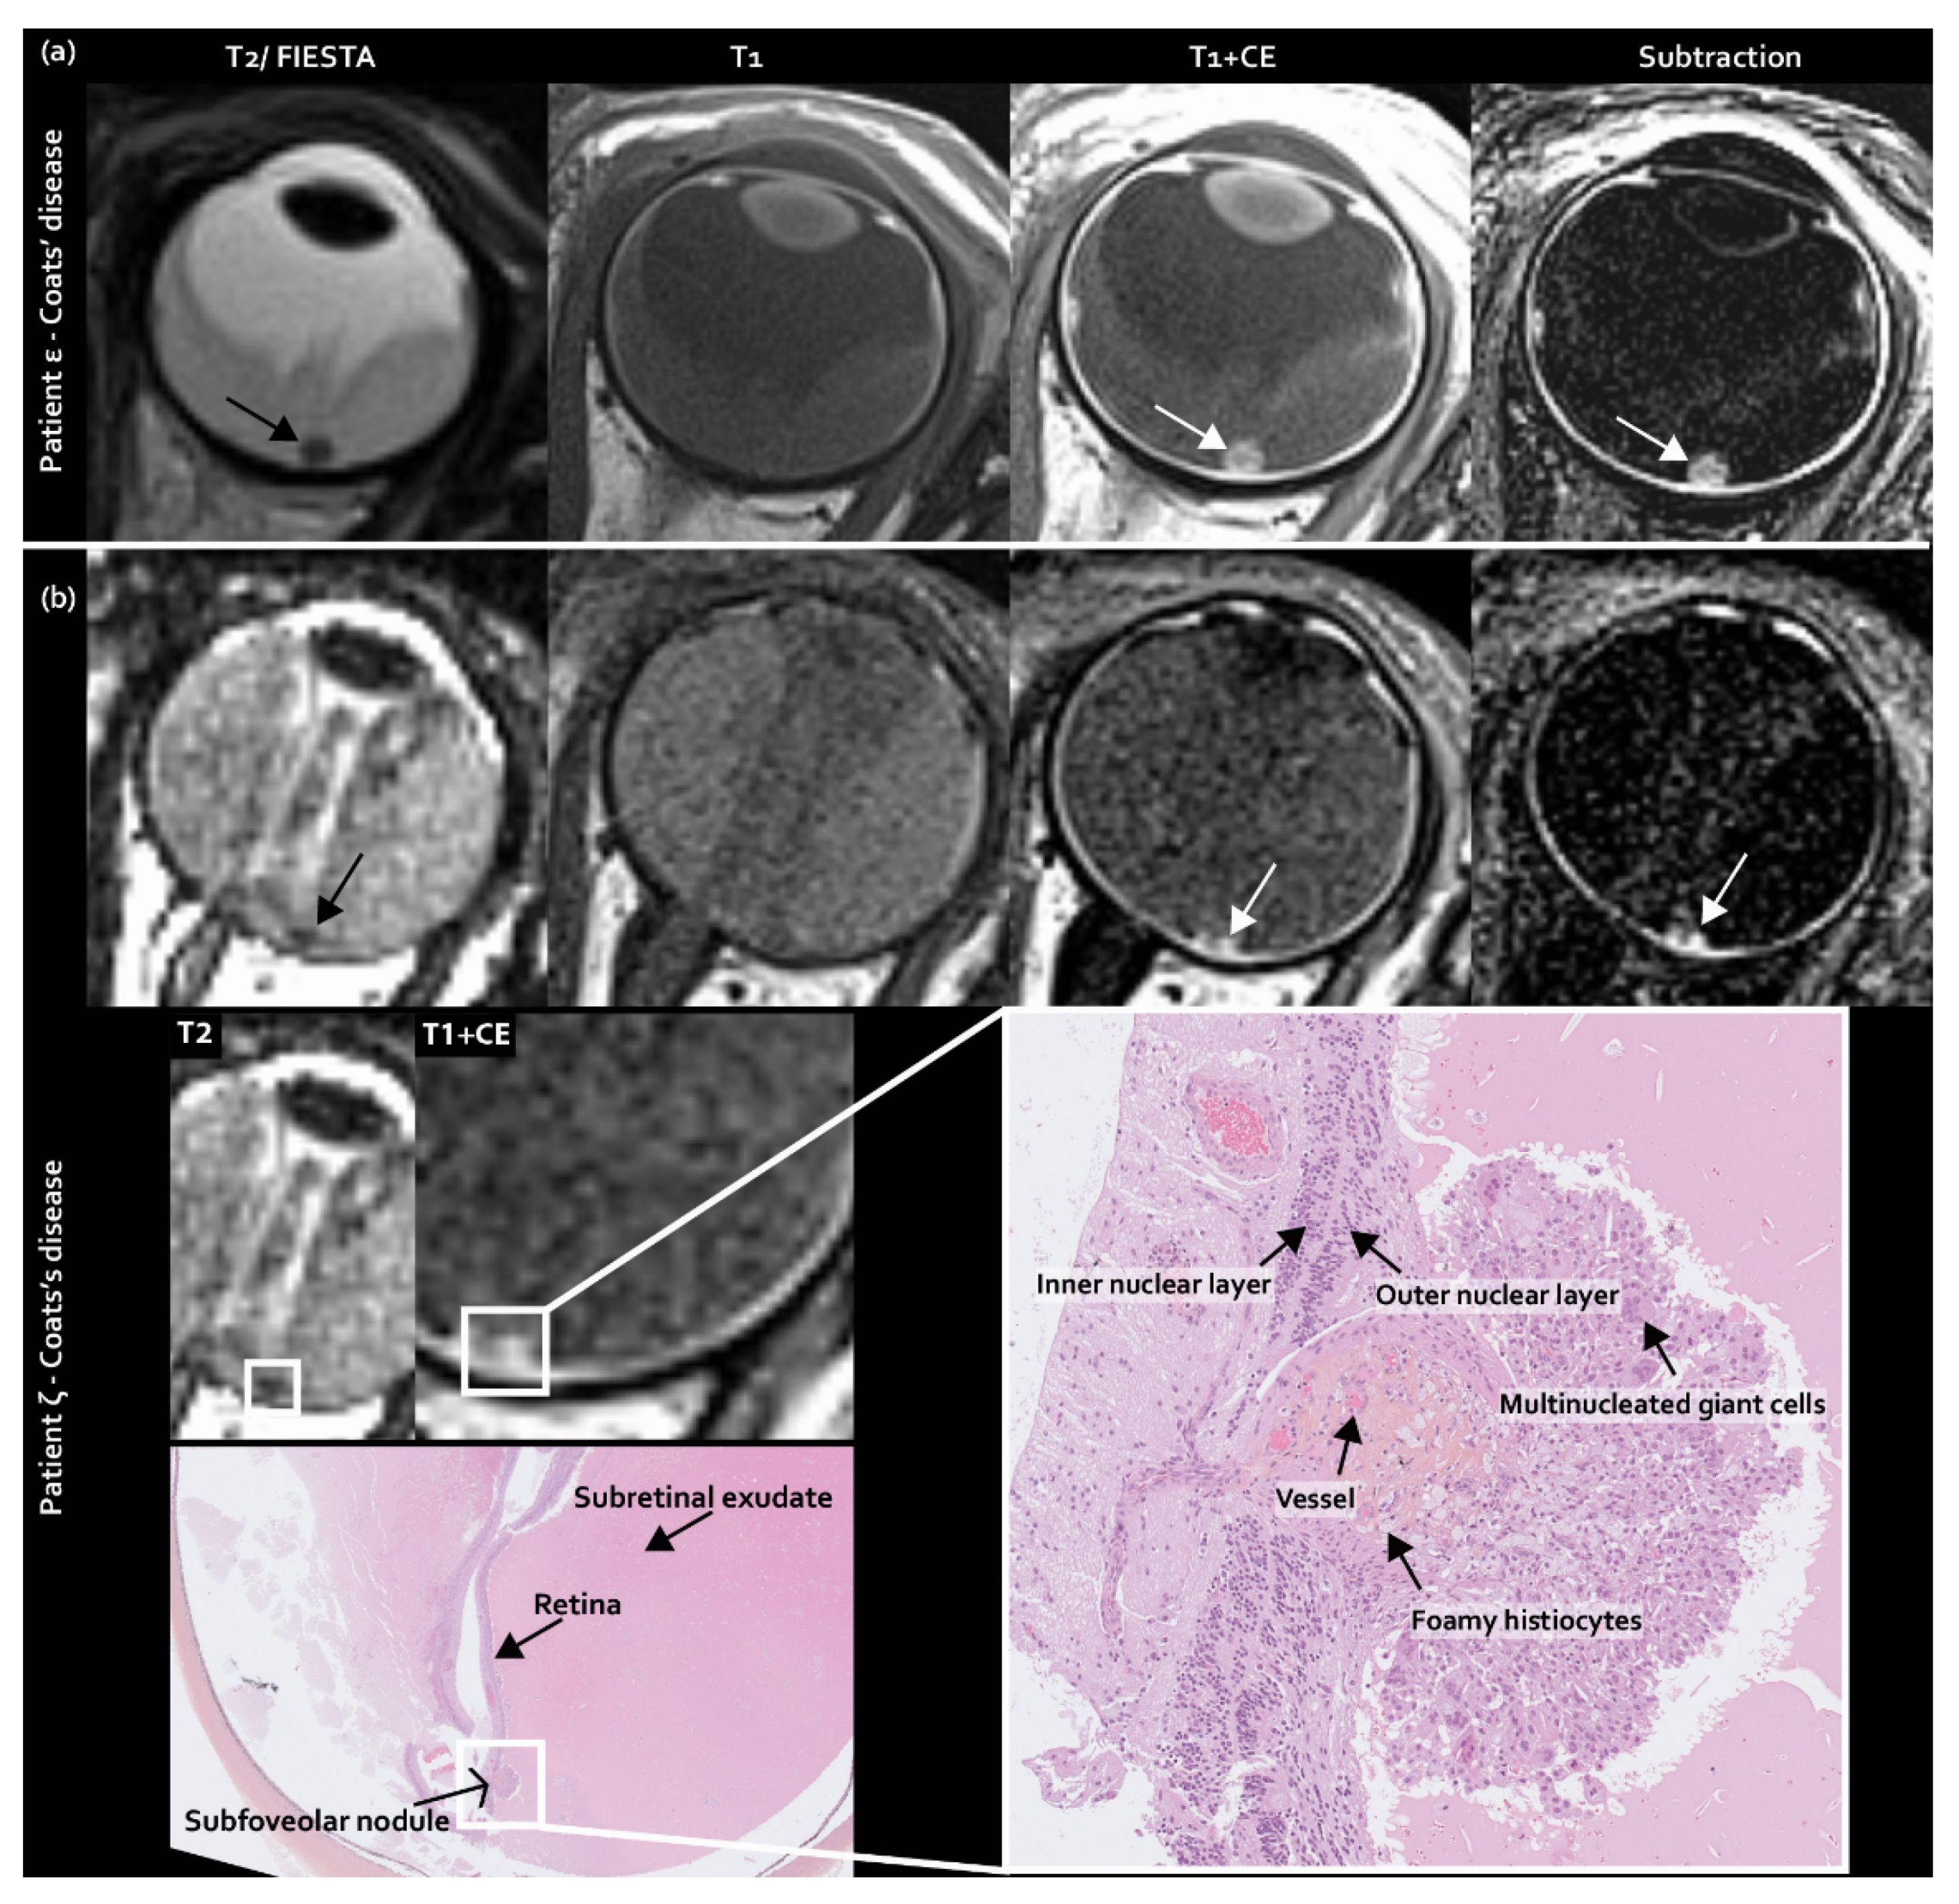

Next to typically non-enhancing tumor seeding in the subretinal space in retinoblastoma, as incorporated in the predefined imaging features list, subretinal enhancing nodules were encountered at the fovea. These nodules appeared to be present only in Coats’ disease in 33% (8/24) of eyes upon post-hoc analysis (Figure 3) and were congruent with subfoveal nodules, as described in ophthalmologic Coats’ disease literature [22].

Figure 3.

Subfoveal enhancing nodules as a newly identified MR imaging feature exclusively found in Coats’ disease: (a) MR imaging of (enhancing) subfoveal nodules in Coats’ disease patient ε; (b) MR imaging of (enhancing) subfoveal nodules with corresponding histopathology of Coats’ disease patient ζ.

Thirdly, enhancing subfoveal nodules were newly identified on MR imaging in Coats’ disease, although a prevalence of 53% is reported in ophthalmologic and histopathologic assessments [22]. Histopathologically, subfoveal nodules contain protein- and lipid-rich material, and they progress over time into macular fibrosis, associated with worse visual outcomes [22]. The subfoveal nodules in this study showed various amounts of enhancement, which was possibly correlated to the degree of fibrosis. Potentially, subfoveal nodules could mimic subretinal tumor seeding in retinoblastoma. However, the key-features to differentiate these two entities are that tumor seeding does not enhance and is not preferentially located at the fovea. The imaging finding of a subfoveal enhancing nodule may therefore provide an important sign in favor of Coats’ disease. In the differential diagnosis, an enhancing granuloma in toxocara endophthalmitis could be considered in the correct clinical context [23].